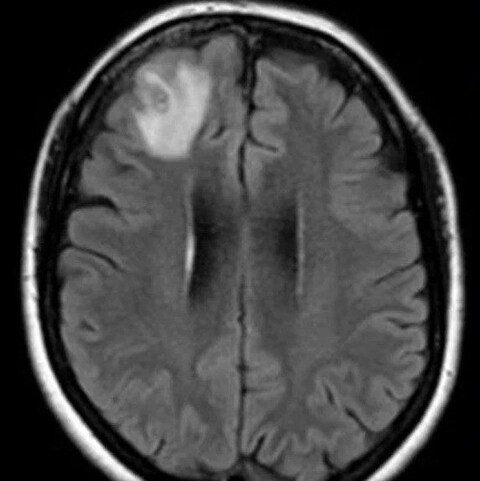

困惑的医生对这名64岁的澳大利亚妇女进行了核磁共振扫描,发现她的大脑前部有一个“非典型病变”。

这种寄生虫在脑部扫描中表现为“线状结构”,随后通过DNA测试进行了鉴定。